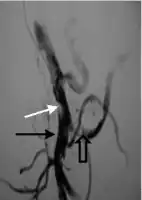

Portal vein thrombosis

Grade III main PVT white arrow

Portal vein thrombosis affects the hepatic portal vein, which can lead to portal hypertension and reduction of the blood supply to the liver.[5] It usually happens in the setting of another disease such as pancreatitis, cirrhosis, diverticulitis or cholangiocarcinoma.[6]